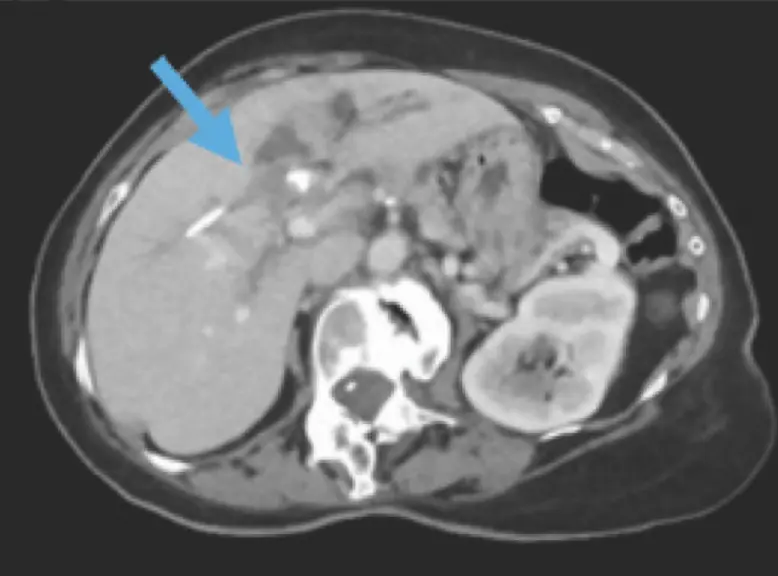

First-in-man histotripsy of hepatic tumors: the THERESA trial, a feasibility study

View Trial InformationSTUDY DESIGN: Prospective, non-randomized, multi-center feasibility trial

SAMPLE SIZE: 8 participants with 11 treated tumors

POPULATION: HCC, intrahepatic cholangiocarcinoma, breast metastasis, colorectal metastases

PRIMARY ENDPOINTS/RESULTS: This feasibility trial demonstrated 100% technical success, observed up to 8 weeks, with no device or procedure related adverse events

STATUS: Complete, published

PUBLICATION: Vidal-Jove J, et al. Int J Hyperthermia. 2022;39(1):1115-1123